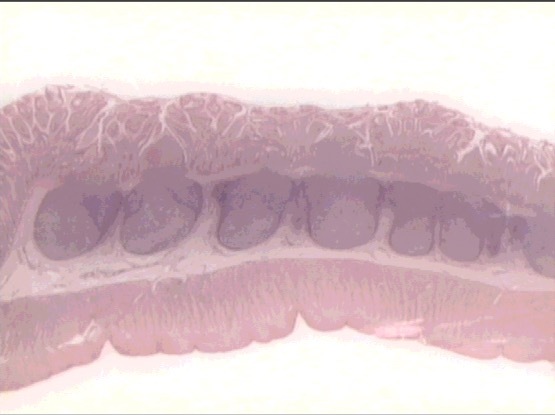

lymphoid nodule

(colon)

solitary lympoid nodule

B-lymphocytes

T-lymphocytes